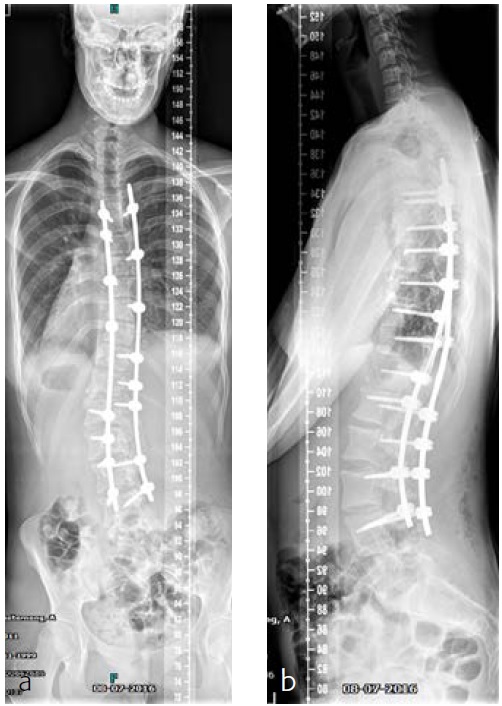

On physical examination a cooperative boy was seen, normal build and height, normal to high paraspinal muscle tone. Standing upright he was off balance to the right. Neurological examination showed absent abdominal skin reflexes bilaterally. The curve was classified as neuromuscular type scoliosis (Fig 6). Due to the curve magnitude, being off balance, and with (severely) limited nonoperative options (Fig 7), surgical treatment was discussed with the family.

He was scheduled for a posterior deformity correction from T4L3. Under general anesthesia, with IONM (TC-MEP) the deformity was corrected. Intraoperatively, an epidural catheter was placed with the tip at T7 for postoperative analgesia.

Mobilisation started the day after surgery. He was discharged the fourth day after surgery. He returned for scheduled follow-up after 7 weeks (Fig 8). He seemed less agitated compared to the period before surgery. He did not seem to have specific limitations.